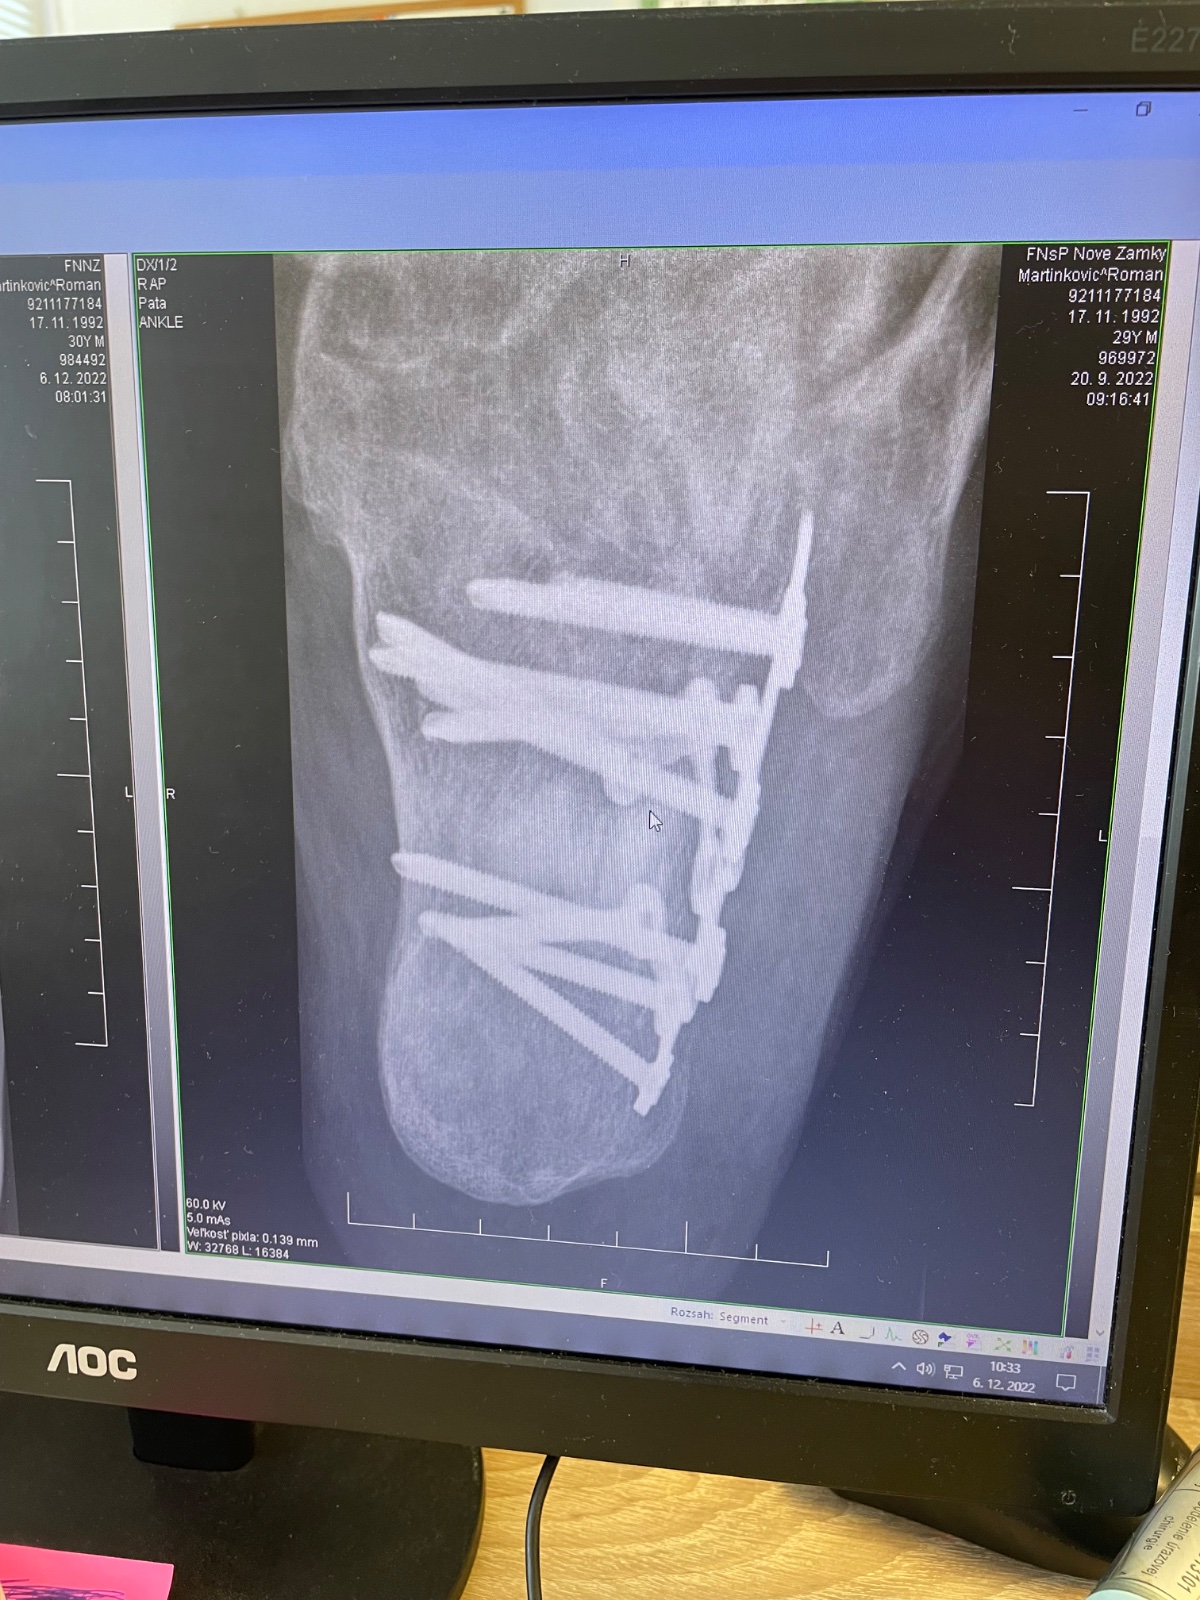

Ahojte,, chcem reagovať Mariane na mail a hlavne držim palce Tvojmu manželovi. Čaka ho beh na dlhú trať. Ja som tiež myslel, že to do dvoch mesiacov dám. Som zhruba rok po operácií a poviem, že kto to raz zažije tak nikdy viac. Radšej zlomená kosť, ale nie trieštivá zlomenina.päty. V prvom rade musí čim skôr začať cvičiť. Ak pôjde do kúpeľov veľký pozor na vodu, nech si to rozdelí s väčším odstupom, nie po sebe. Dobre bude plávanie a cyklistika, ale s mierou. V žiadnom prípade nech nedáva saunu. V nohe má Titan a ak mu ho nebudú vyberať, nevieš čo môžu spôsobiť zahriatie. Predsa sú tam skrutky, ktoré pri povolení môže spôsobiť zápaľ. Držim palce.

Zdravím, no môj snímok vyzerá podobne, tiež zošrobované a samý kov, ako noha Robocopa. Som osemnásť mesiacov a svetlo stále nevidím. Prejdem, tak kilometer a potom koniec. Teraz som bol na konzultáciách v NR a potvrdené KE, že má čaká ďalšia operácia. Členok, že vraj s najväčšou pravdepodobnosťou bol poškodený roztrieštnou pätou. Teraz je tam kov, ktorý bude nutné odstrániť a s tým spojené možné komplikácie a vyplnenie štepom.